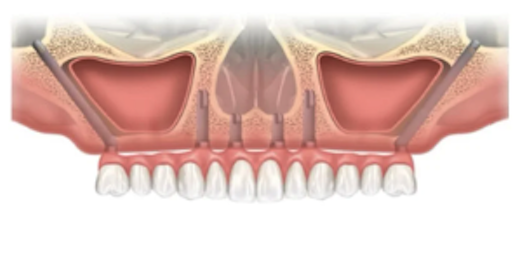

①前歯の部分は長さが10mm以上のインプラントを入れられる量の骨がある

②奥歯の部分は長さが13mm以上、直径が4mm以上のインプラントが入れられる量の骨がある

③唇側の骨が2mm以上ある

※上記の条件を満たさない場合は、インプラントを1~2本追加で埋入する場合があります。(オールオン5・オールオン6)さらに場合によってはザイゴマインプラントになることもあります。